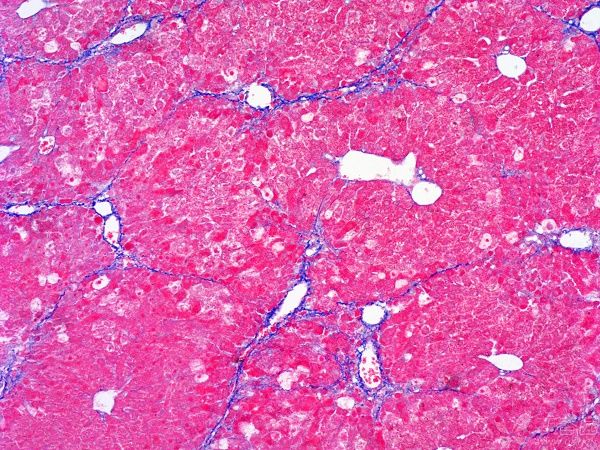

這種染色方法通過(guò)特定的化學(xué)反應(yīng)和染料選擇,使得不同類型的纖維在顯微鏡下呈現(xiàn)出不同的顏色,從而便于研究者對(duì)組織結(jié)構(gòu)和病變進(jìn)行準(zhǔn)確的觀察和分析。

㈠:MASSON染色通過(guò)特定的染色劑:能夠使膠原纖維和肌纖維分別呈現(xiàn)出不同的顏色,從而實(shí)現(xiàn)對(duì)這兩種重要組織成分的精準(zhǔn)區(qū)分。這對(duì)于后續(xù)的組織學(xué)研究具有非常重要的意義。

㈡展示組織纖維化程度:作為一種重要的組織纖維化觀察方法,MASSON染色能夠清晰地顯示出組織中的纖維結(jié)構(gòu),包括膠原纖維的排列、形態(tài)和數(shù)量等。通過(guò)對(duì)這些信息的觀察和分析,研究人員可以準(zhǔn)確地評(píng)估組織的纖維化程度,為進(jìn)一步的研究和治療提供重要依據(jù)。